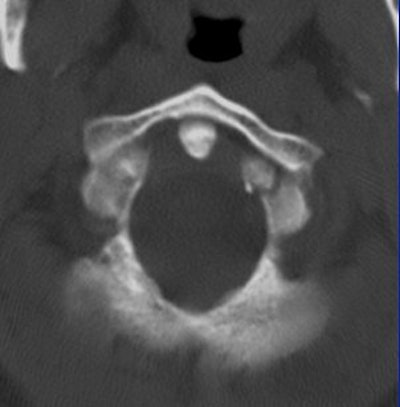

The 0.5-mm slices offer fine bone detail, but pay a price on the soft-tissue images in terms of soft-tissue differentiation. Whereas the thicker (5-mm) slices fail to show the bone detail of the fracture well, but possess greater contrast resolution on the soft-tissue window to differentiate spinal cord from surrounding spinal fluid.